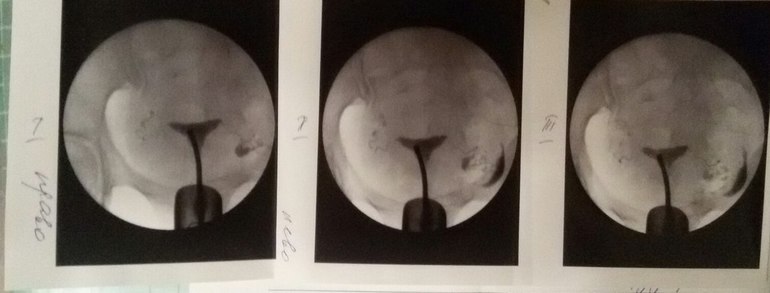

ГСГ Снимок. Кто что думает?

Сделала ГСГ в октябре. Врач сказала все норм. Вчера ходила к другому доктору он мне говорит что правая труба непроходима. На первом снимке самый левый снимок.

Сделала ГСГ в октябре. Врач сказала все норм. Вчера ходила к другому доктору он мне говорит что правая труба непроходима. На первом снимке самый левый снимок.

На втором снимке правая труба слева.

справа от меня 100% проходима, вышел контраст в брюшную полость

а слева не видно что контраст вышел из трубы, где-то затор

плюсуюсь. слева труба частично проходима, тк контраст по трубе прошел, но почему то не вышел

я не по сторонам а по снимку....

справа проходима видете жидкость вылилась? а с лева не вылилась... значит слева не проходима... то есть правая труба